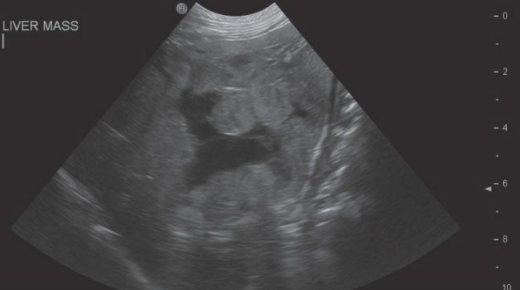

- 흉부 질환 식별 X → 복부 질환 식별 (복부 초음파)